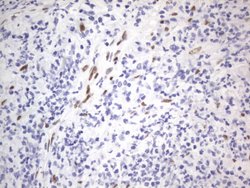

RBFOX1 Mouse anti-Human, Clone: OTI4F9, lyophilized, TrueMAB™

| Immunohistochemistry (Paraffin), Western Blot | |